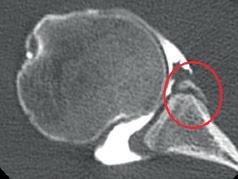

BEELDVORMING

De onderliggende reden van instabiliteit moet steeds achterhaald worden, dit om een goede behandeling te kunnen voorstellen. Na een goed klinisch onderzoek, vormt beeldvorming de volgende essentiële stap. De klassieke röntgenfoto's worden steeds gebruikt voor de initiële aanpak van schouderinstabiliteit. Naast de luxatierichting kunnen we op RX ook tekens van andere diverse schouderpathologieën nagaan o.a. gewrichtsspleetvernauwing, hoogstand van de humeruskop suggestief voor cuff-artropathie, fracturen zoals Hill Sachs (Fig. 6) en bony Bankart letsel (Fig. 7), osteofyten, subchondrale cyste, weke weefsel ossificatie en calcificaties.

In de verdere oppuntstelling van schouderinstabiliteit kan een arthro-CT of arthro-MRI aangevraagd worden. Het intra-articulaire contrastvloeistof creëert een distensie van het gewrichtskapsel en maakt visualisatie van – zelf de kleinste- labro-ligamentaire letsels zichtbaar. De arthro-CT heeft hierin het voordeel een betere en scherpere resolutie te kunnen bieden, samen met een betere visualisatie van kleinere botfragmenten. Op zeer jonge leeftijd

Fig. 6: Arthro-CT rechterschouder met Bankart letsel (rode pijl) en Hill Sachs letsel (rode ster) Fig. 7: Arthro-CT rechterschouder met Bony Bankart (rode circkel)